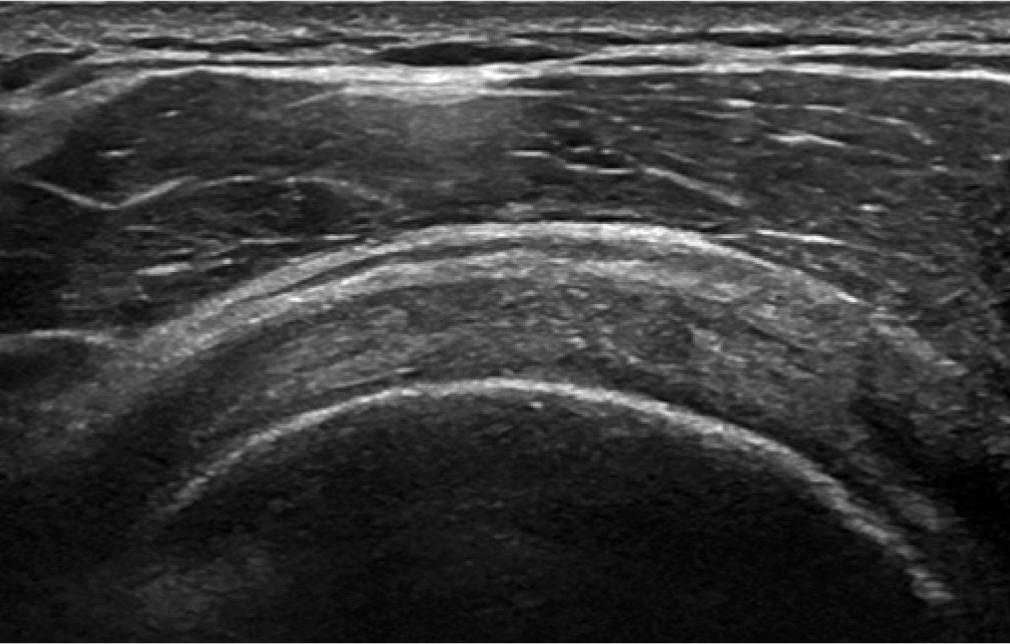

The bursa should be seen as three parallel stripes. The top and bottom should be of high echogenicity compared to the low central stripe (Fig. 1). If the lower stripe is not seen, then this would imply a bursal surface supraspinatus or infraspinatus fraying (Fig. 2). If the stripes are not clear in outline, appearing blurred, then the presence of an adhesive bursitis should be considered (Fig. 3). In a child or young adult, the central stripe may be very thin, and the bursa may appear as one stripe if the resolution of the ultrasound machine is poor.

The subdeltoid subacromial bursa is not as distinct on the right of the image compared to the left